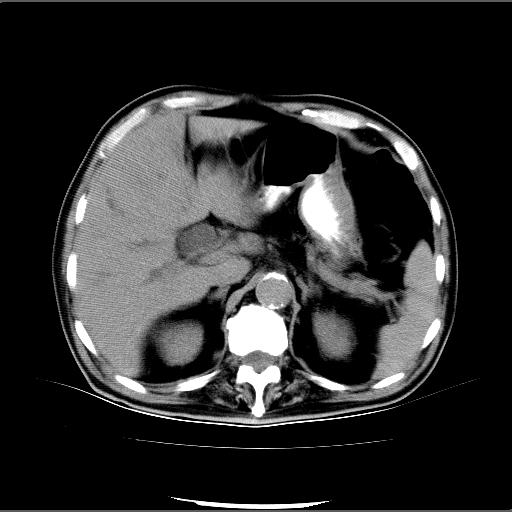

患者男82岁,黄染,发热10天,无腹痛。

1胆总管下端结石伴肝内外胆管扩张;2胆囊颈部结石伴胆囊积液

胆囊多发结石,胆囊积液;胆总管中下段结石,中上段扩张。

胆总管下段结石伴胆道系统扩张;胆囊炎伴胆囊结石.

1、胆总管壶腹部结石并胆总管、胆囊及肝内胆管扩张。2、胆囊多发结石。3、两下胸膜局限性增厚。4、胃体部大弯侧胃壁稍厚,建议:多量饮水后增强ct扫描除外占位性病变。

此病例有结果了:患者术后为:胆总管下段结石伴胆道系统扩张;胆囊炎伴胆囊结石。

各位战友分析的都很正确,是一个典型的病例。